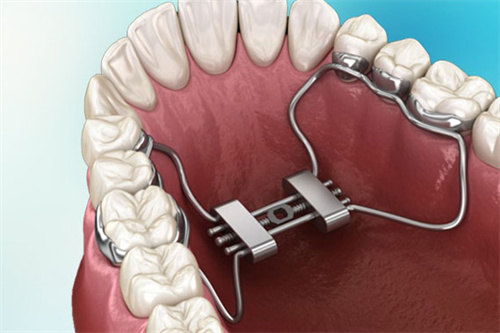

固定式扩弓器价格范围:5000元至15000元(一副)

固定式扩弓器:高端固定式扩弓器价格可达10000元以上(一副),通常采用优质材料和精细制作工艺,适合牙齿畸形程度较重或对矫正结果有较高要求的患者。